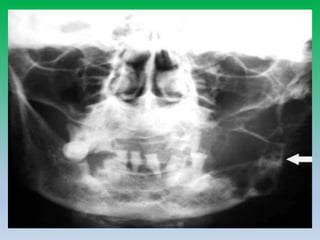

Cropped panoramic radiograph

showing

well defined corticated radiolucency

in the posterior

body of mandible

Axial CT demonstrates a well defined

lingual cortical defect in the posterio

mandible